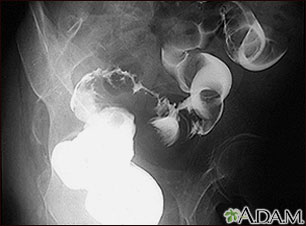

Sigmoid colon cancer, x-ray

A barium enema in a patient with cancer of the large bowel (sigmoid area).